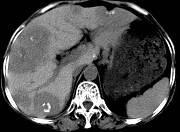

- 单项选择题女,55岁, 腹胀,肛门闭气, 消瘦乏力,肝区疼痛, CT检查如图,最可能的诊断为 ( )

A、多发性肝脓肿

B、肝癌肝内转移

C、肝淋巴管瘤

D、肝脏囊腺瘤

E、结肠癌肝转移